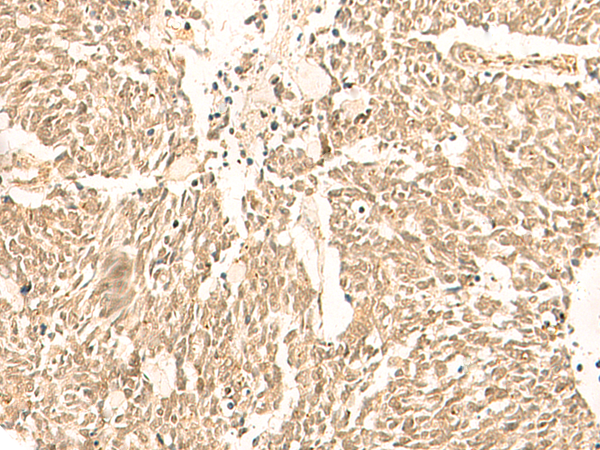

分类: 科研抗体货号: P02975别名: L34应用: WB,IHC反应种属: Human, Mouse, Rat